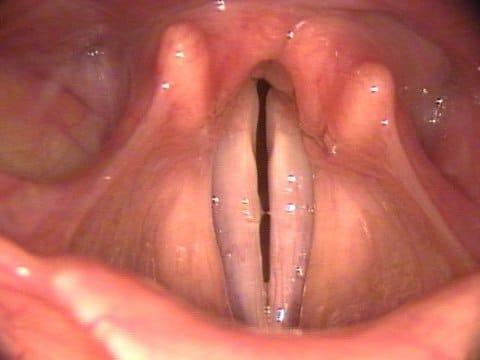

Перед началом лечения важно разобраться в особенностях заболевания. Ларингит имеет множество признаков, похожих на фарингит. Основное различие между этими недугами заключается в локализации воспалительного процесса. При фарингите воспаляется слизистая оболочка глотки, тогда как при ларингите инфекция затрагивает голосовые связки и гортань.

- покраснение гортани и отек слизистой в области воспаления;